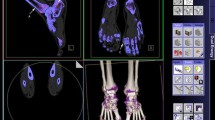

Gout imaging—urate detection

DECT has been documented to exhibit higher sensitivity (up to 89%) and specificity (up to 100%) to reach the diagnosis of gout when compared with other imaging modalities [40,41,42,43]. The use of DECT is opening the possibilities of new diagnostic scenarios by identifying, mapping, and monitoring crystal deposits [43]. DECT takes advantage of the different Dual energy index (DEI) of calcium and urate. Once these materials have been differentiated, each can be uniquely color-coded (Fig. 2). As a matter of fact, the technological advancements of DECT and validation of dedicated gout-tools resulted in a robust imaging modality that has been included in the 2015 Gout classification criteria [44]. Furthermore, the accuracy of DECT for gout diagnosis can be substantially different in different phases of the disease. In fact, while it reaches accuracy of 100% in active phase of chronic gout with arthritis and tophus, it results positive in 36–80% of patients with acute symptomatic gout flare (< 6 weeks) and in 62–100% of symptomatic patients with intercritical gout (less than 3 years) [45]. Of note, radiologists must be aware of possible artifacts when utilizing DECT gout protocols. One of the main studies on artifacts related to the study of gout in DECT was conducted by Mallinson et al. who analyzed DECT of 50 subjects with presumed gout in order to stratify the most frequent types of artifacts evaluating multiple joints [46]. Artifacts were observed in 90% of scans including:

Nail bed artifacts these artifacts can be observed in the nails of the feet (88% of subjects) with less frequency in the hands (4 % of subjects). The most plausible explanation was the similarity of DEI values of keratin and monosodium urate.

Skin artifacts these artifacts, again, were common in the feet (about 40% of cases) but less in the hands (about 4% of cases). No skin artifacts were found on the knees or elbows. One reason may be the greater amount of calloused skin in the foot. However, these artifacts were observed old scanners images, having become negligible over time in the most recent machines.

Submillimeter artifacts believed to be a form of noise. However, it is necessary to be aware of their veracity and to consider them as gouty deposits if they are found in an anatomical structure such as in tendons. Again, this issue has been overcome in the most recent scanners.

Anyway, despite these artifacts can be encountered in DECT gout protocols, they are readily recognized, so false-positive findings quite rare. A further artifact was found in the study corresponding to the calcific vessels. Three out of four patients with this type of artifact showed further similar artifacts at the level of the arteries of the lower limbs, suggesting a possible meaning of gouty deposit, the statistical significance of which, however, could not be demonstrated due to the small sample. Indeed, it has been postulated that urate might contribute to the dysfunction of vascular endothelium [47].

Some limitations of DECT in gout imaging must be pointed out. In addition to the abovementioned artifacts, time-consuming post-processing, and non-negligible radiation exposure, DECT is not able to detect crystal deposits smaller than 2 mm located over the cartilage or within the effusion [48]. Then, it is less sensitive than MRI and ultrasound in detecting synovitis, tenosynovitis, and BME [49, 50]. Last, its accuracy decreases in deeper joints (i.e., spine or hip) due to the poor penetration of low voltage beam.